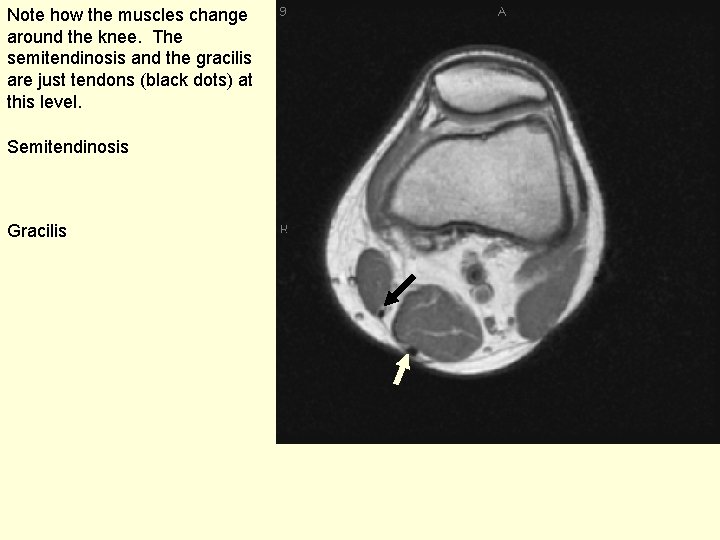

Note how the muscles change around the knee. The semitendinosis and the gracilis are just tendons (black dots) at this level. Semitendinosis Gracilis